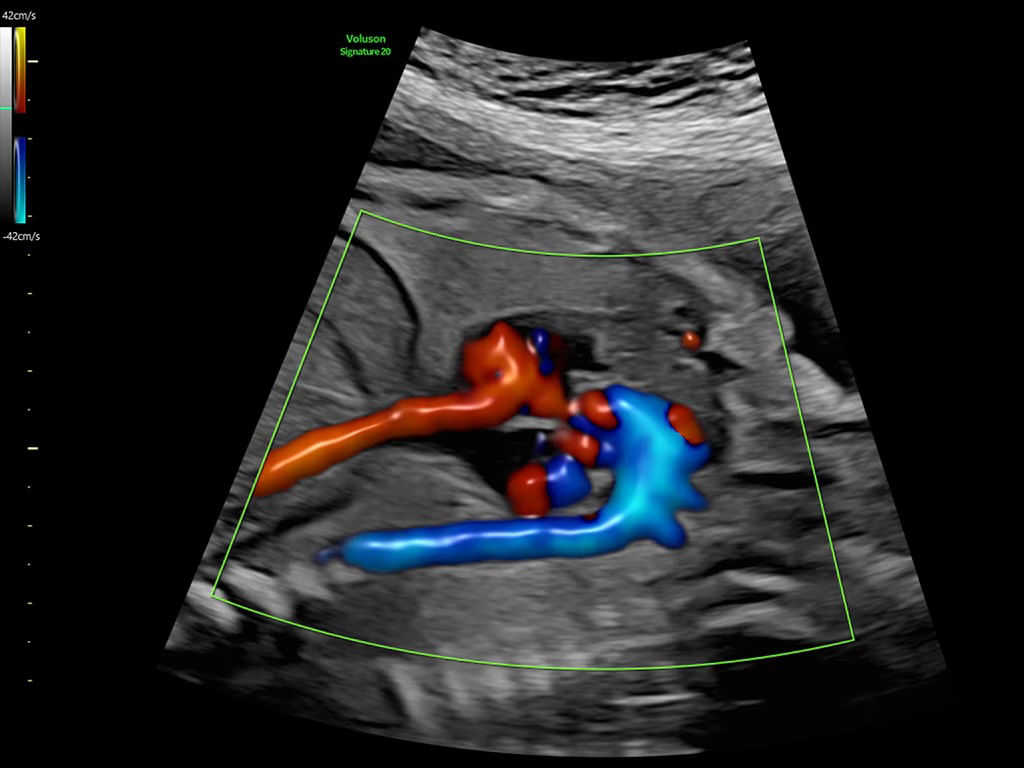

Reduce color and Doppler exam time by 56% with Flow Profiles

Next level color Doppler that delivers exceptional sensitivity for easy, fast visualization of blood flow, displaying a 3D like appearance as seen in this 27-week fetal heart.